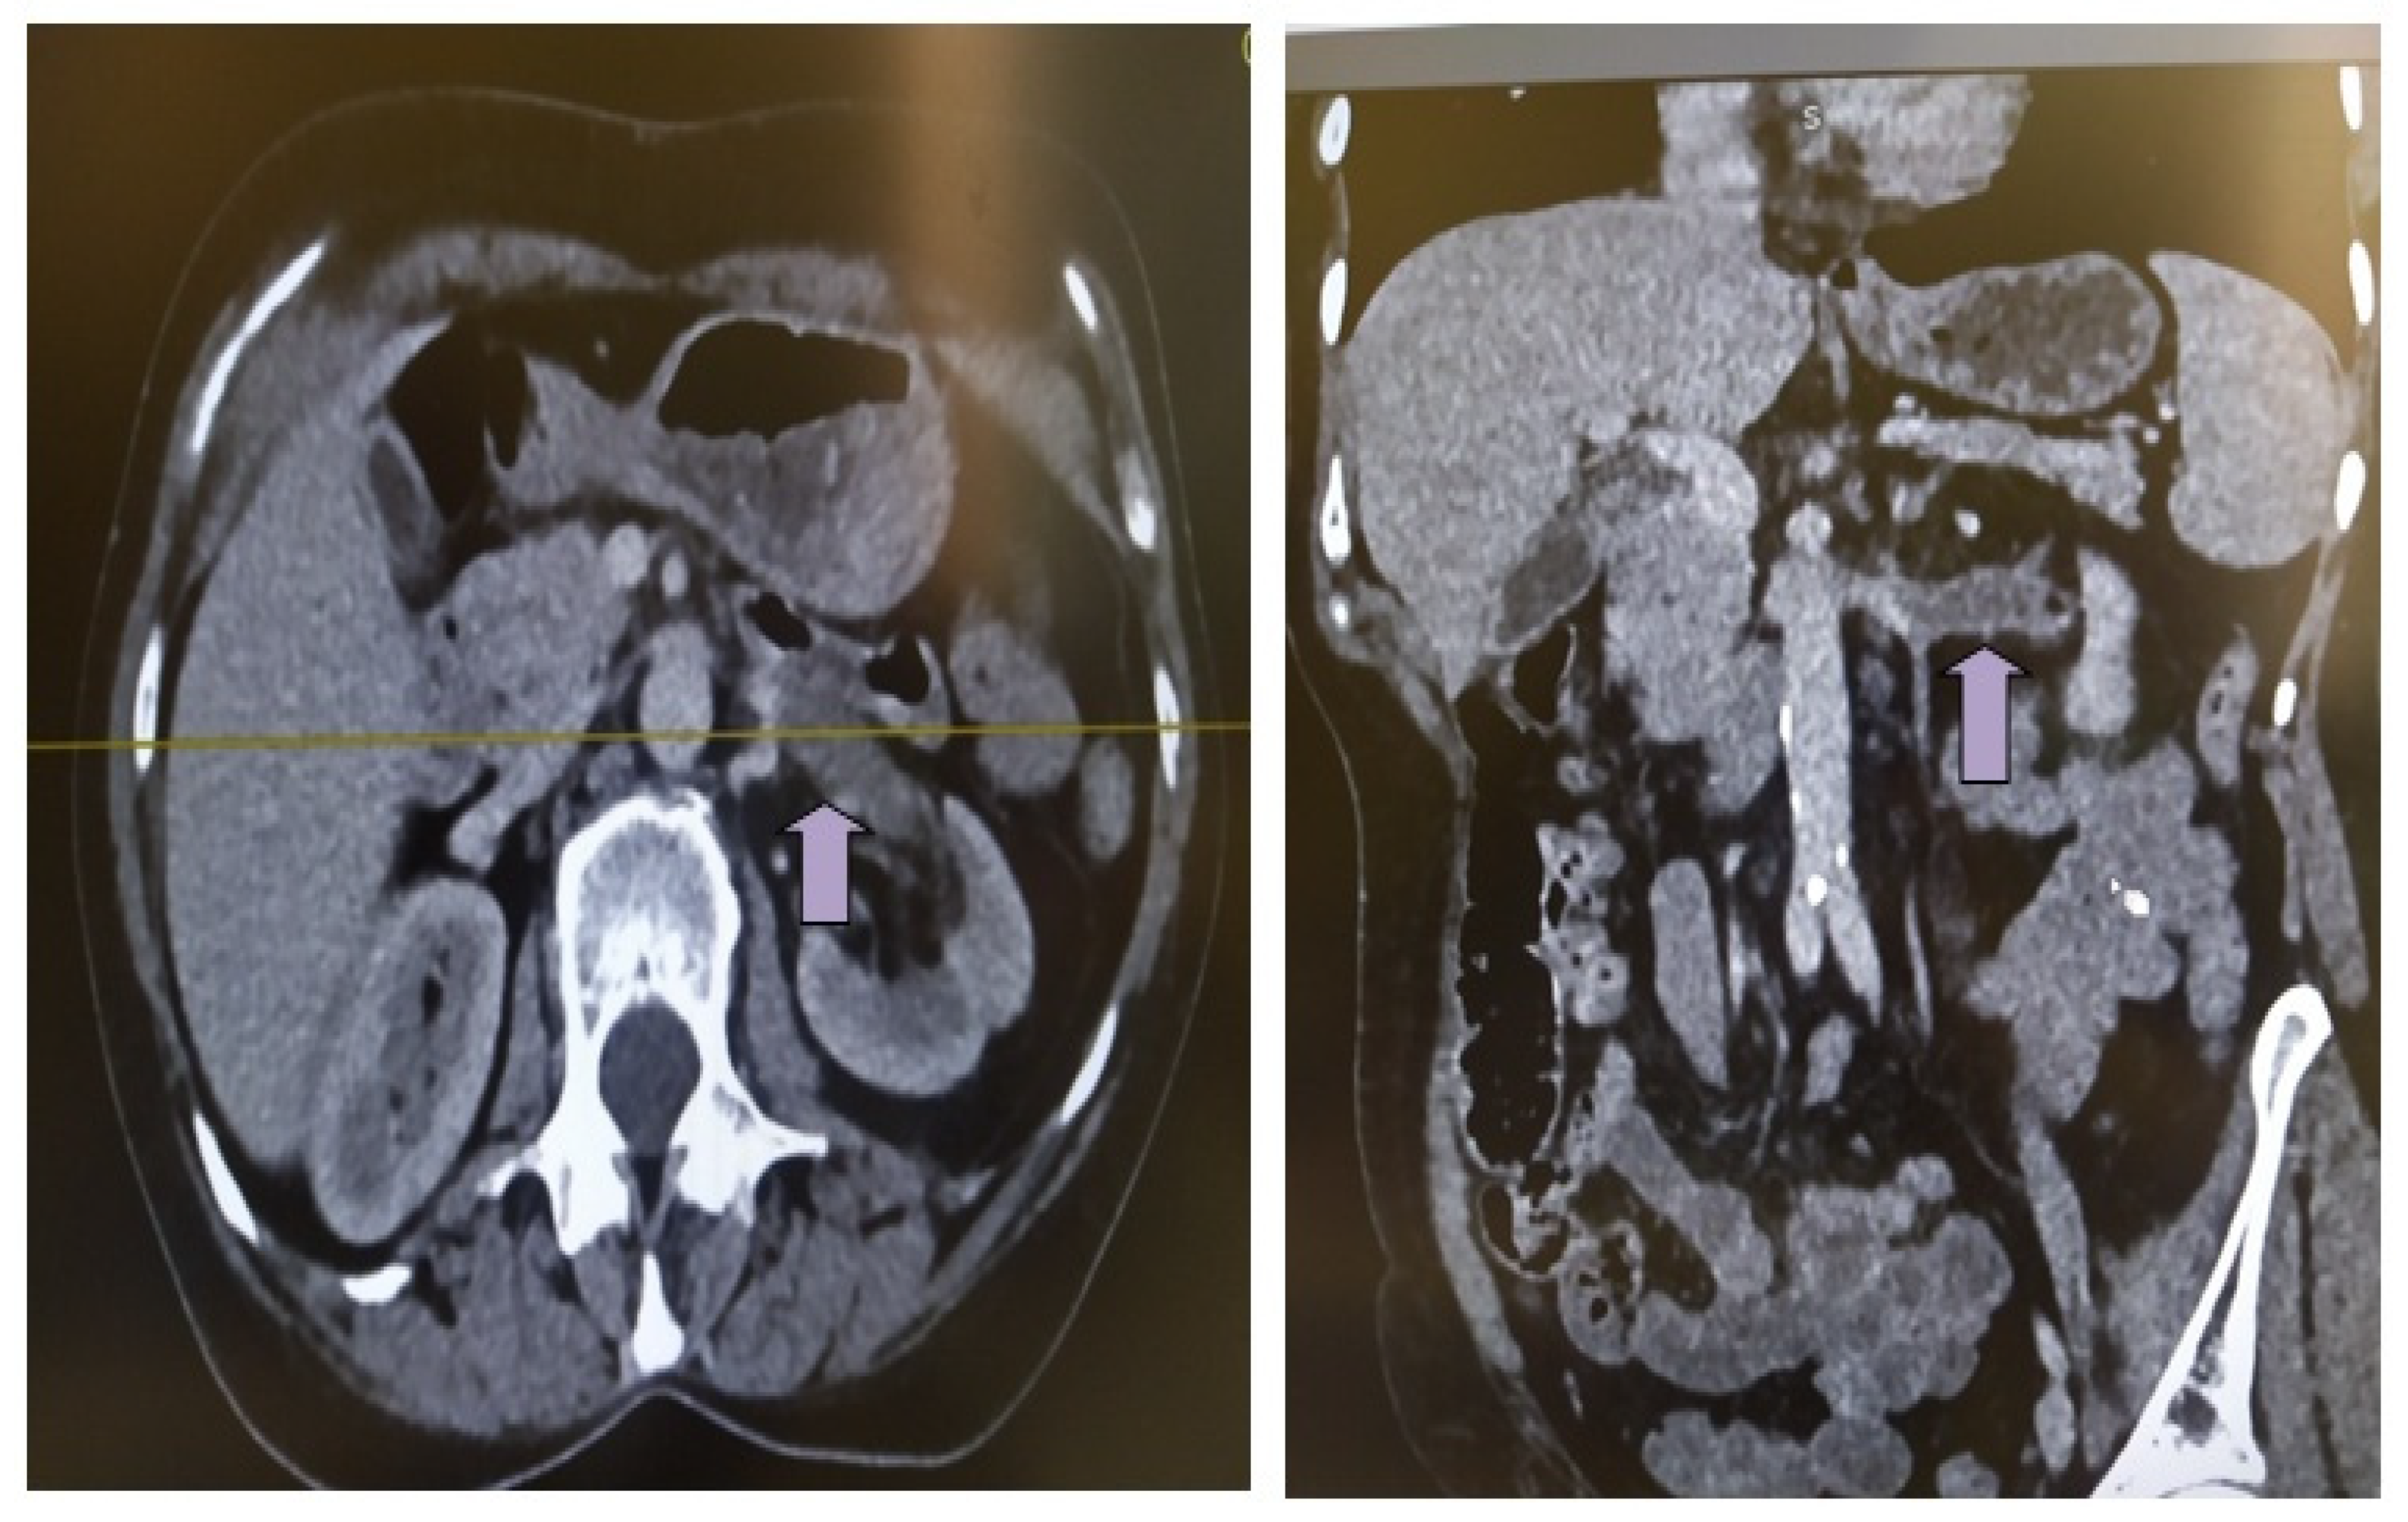

2. Case Description